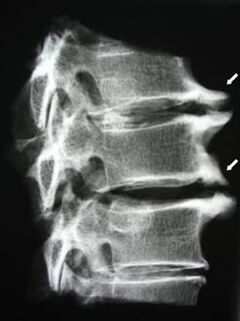

İlk aşamalarda, osteokondroz MRI kullanılarak tespit edilir. Daha sonra patoloji radyografi kullanılarak teşhis edilebilir. Servikal omurganın radyografilerinde omurlar arasındaki mesafede bir azalma, faset eklemlerdeki patolojik değişiklikler ve osteofitoz fark edilir hale gelir.

| Servikal osteokondroz | Bir veya daha fazla omurga hareket segmentinde patolojik değişikliklerin ortaya çıkması. Omurga hareketliliğinin bozulması, miyofasyal ağrı sendromlarının gelişimi ve omurilik köklerinin sıkışması | Başın arkasına ve üst ekstremitelere yayılan, servikal bölgede ağrı, parestezi ve motor bozukluklar. MR ve radyografilerde omurgadaki karakteristik değişikliklerin tespiti (osteofit, omurlar arasındaki mesafenin azalması, omurlararası eklemlerde hasar belirtileri) |